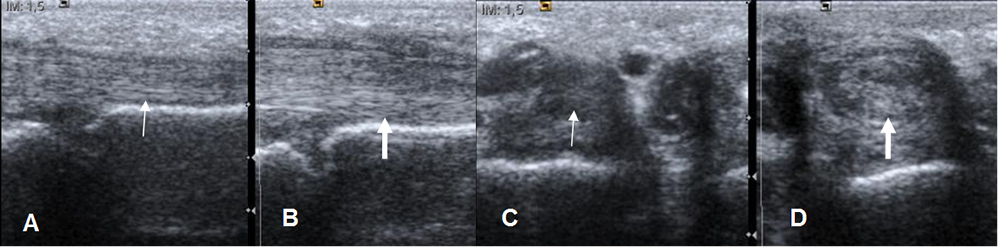

Con la ecografía se puede encontrar engrosamiento del tendón y alteración de su patrón fibrilar por tendinitis o el tendón rodeado por líquido por tenosinovitis. (Fig 89).

Fig 89. Tendinitis.

A: Ecografía sagital y C: ecografía axial. Tendón flexor del 3º dedo normal.

B: Ecografía sagital y D: ecografía axial. El tendón del 4º dedo está engrosado y con pérdida de su patrón fibrilar, por tendinitis.